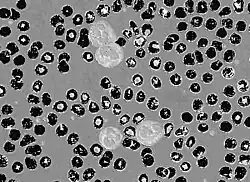

Circular thresholding is an algorithm for automatic image threshold selection in image processing. Most threshold selection algorithms assume that the values (e.g. intensities) lie on a linear scale. However, some quantities such as hue and orientation are a circular quantity, and therefore require circular thresholding algorithms. The example shows that the standard linear version of Otsu's method when applied to the hue channel of an image of blood cells fails to correctly segment the large white blood cells (leukocytes). In contrast the white blood cells are correctly segmented by the circular version of Otsu's method.